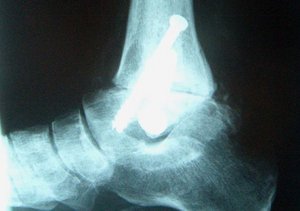

Wenn Sie Ihr Chirurg oder Orthopäde zu einer ambulanten Vorstellung überwiesen hat, werden Sie nach Ihren Beschwerden befragt, körperlich untersucht und das Ausmaß des Sprunggelenkverschleißes durch Röntgenaufnahmen festgestellt. Gelegentlich wird mit einer Test-Injektion die Schmerzursache genauer lokalisiert. Voraussetzung für den Einbau einer Sprunggelenkprothese ist nämlich ein intaktes unteres Sprunggelenk, eine normale Gelenkstellung im Rückfuß und eine gute Knochensubstanz des Sprungbeines (Abb.2).

Im Vergleich zu Knie- und Hüftprothesen müssen Prothesen für das Sprunggelenk sehr viel seltener eingebaut werden. In unserer Klinik wird eine zementfreie Prothese bestehend aus den drei Komponenten Unterschenkelteil, Sprungbeinteil und Kunststoff-Inlay eingesetzt (Abb.3).

Die Prothesenkomponenten werden durch Anwachsen des Knochens an die Prothese verankert.